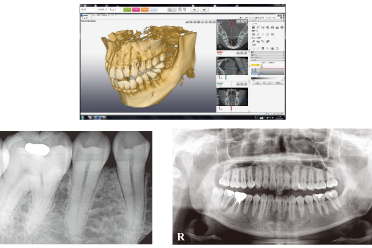

抜歯に際しては、必要に応じてCTレントゲンを用いて親知らずの位置や生え方を詳しく確認した上で、安全に処置が行われます。